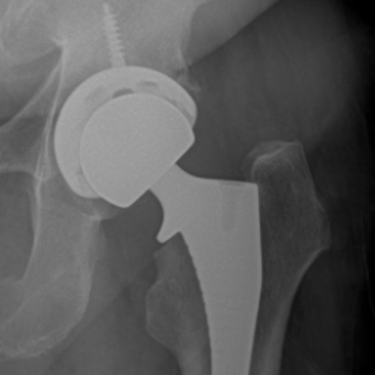

Hip resurfacing is a bone-preserving alternative to total hip replacement, designed for younger, active patients with hip arthritis. Unlike traditional hip replacement, which removes the entire femoral head, hip resurfacing reshapes and caps the existing bone, preserving more of the patient’s natural anatomy.

Hip resurfacing involves placing a metal cap over the reshaped femoral head and lining the hip socket with a metal cup. By preserving the femoral neck and most of the natural bone, this procedure may allow for more natural movement and easier revision if future surgery is needed.